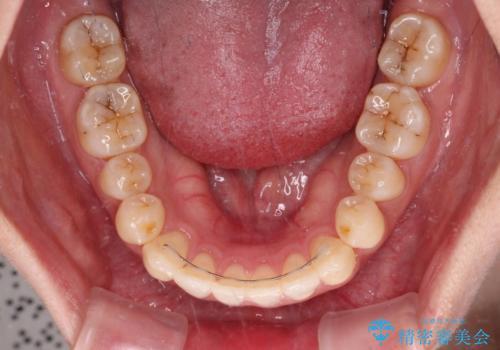

すきっ歯とオープンバイトをインビザラインで改善

- 前歯の上下スペースと前歯の隙間を気にして来院された患者様です。

インビザラインにより上下の前歯の隙間を閉じていくこととしました。

上下の隙間に舌が入り込むことが、すきっ歯やオープンバイトの原因であったため、舌の筋肉のトレーニングも並行して行い、後戻りの抑制を図りました。